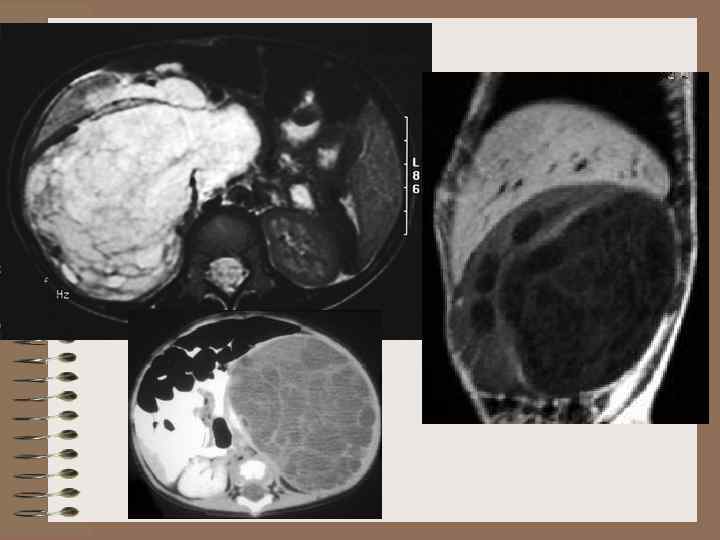

мультилокулярная киста кистозная аденома, кистозная лимфангиома, кистозная гамартома, мультилокулярная кистозная аденома, мультилокулярная кистозная нефрома, кистозная опухоль Вильмса, поликистозная нефробластома, дифференцированная нефробластома, сегментарная поликистозная почка, опухоль Перельмана, доброкачественная кистозная нефрома, аденоматозная поликистозная опухоль Гистологически варьирует от доброкачественной до высокозлокачественной • Нестыковка мета- и мезонефроса в области одного из сегментов почки • Замещение части почки многокамерной, не сообщающейся с ЧЛС кистой • Другая часть почки развита нормально • Процесс односторонний • Содержимое кист однородное • Могут быть кальцинаты в стенках кист

Мультилокулярная киста

Многокамерная дизэмбриональная киста почки

Мультилокулярная киста

Мультилокулярная киста Почечно-кл. рак